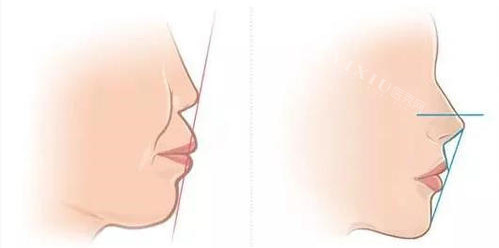

在矫正效率方面,自锁牙套展现出了强大的优势。它能够实现轻力持续矫正,每月牙齿移动速度可达 0.8 - 1.2 毫米,相比之下,非自锁牙套的矫正力相对较弱。临床数据表明,自锁牙套的矫正系统能使疗程比非自锁牙套缩短 3 - 6 个月。对于复杂的病例,如重度拥挤或深覆盖等情况,自锁牙套逐步释放的矫治力能更好地控制牙根位置,实现更准一些的矫正。

非自锁牙套虽然在矫正效率上稍逊一筹,但它在一些需要精细调整的复杂病例中也有其独特的价值。不过,它需要频繁调整结扎力度,这可能会延长整个治疗周期。